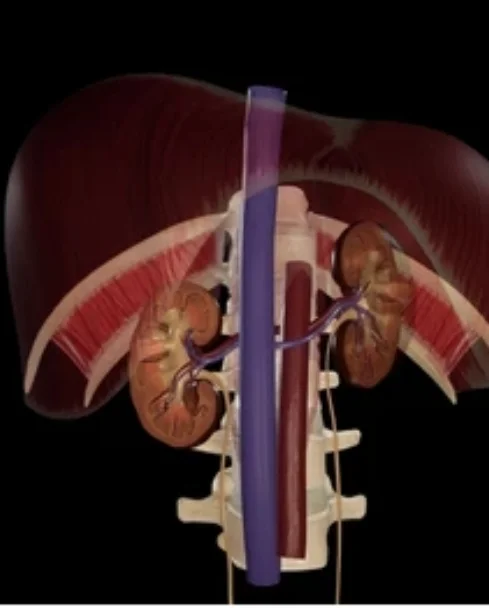

Retroperitoneal tumors develop in the space behind the abdominal organs, close to vital structures such as major blood vessels, kidneys, nerves, and intestines. Due to their location, these tumors often grow silently and are detected at an advanced stage. Under the care of Dr. Anuj Suketu, patients receive specialized evaluation and carefully planned surgery for retroperitoneal tumors. Each procedure is performed with precision, aiming for complete tumor removal while preserving nearby organs and maintaining quality of life.

Open Retroperitoneal Surgery

Preferred for large or complex tumors

Allows direct visualization of major vessels and organs

Enables complete tumor removal with safe margins